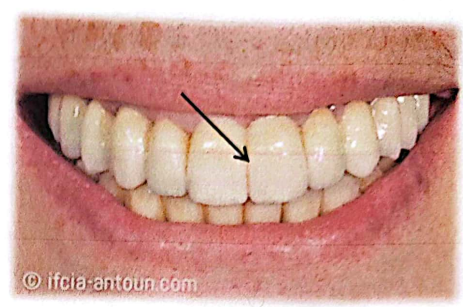

IV.3. Intérêt de la temporisation :

Les prothèses transitoires sont un moyen obligatoire pour rétablir la santé bucco-dentaire. Elles sont indispensables en cas de tissu gingival inflammatoire avant l’élaboration des prothèses définitives.

Fonctions vis-à-vis du parodonte :

- Maintien de la gencive marginale en position physiologique.

- Facilitation de la cicatrisation des tissus parodontaux.

- Contrôle de la stabilité du parodonte avant la prothèse permanente.

- Anticipation de la forme de la prothèse permanente et évaluation du besoin de chirurgie parodontale esthétique.